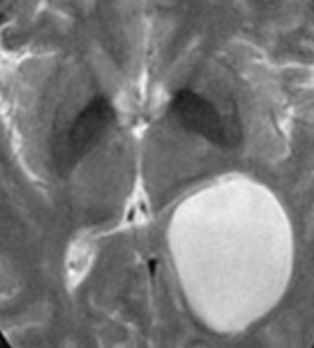

Дермоидные кисты встречаются реже эпидермоидных, составляя около 0,3 % от внутричерепных образований. Обычно выявляются в возрасте между 10 и 20 годами. Морфологически от эпидермоидов их отличает наличие эктодермальных элементов - волосяных фолликулов, потовых желёз и т.д. Типично они расположены по средней линии (в отличие от эпидермоидов, которые чаще внеосевые): в супраселлярной цистерне, субфронтально, вокруг моста и, очень редко парапиниально, периорбитально, в IV желудочке, в области конского хвоста и интрадиплоидно. От эпидермоидных кист на МРТ головного мозга их отличает только выраженная неоднородность структуры, кроме того, они всегда яркие на Т1-взвешенных МРТ головного мозга за счёт большого содержания липидов. При разрыве и прорыве в субарахноидальное пространство в нём появляется уровень, на Т1-взвешенных МРТ головного мозга светлый жир плавает на ликворе.

Дермоидные кисты встречаются реже эпидермоидных, составляя около 0,3 % от внутричерепных образований. Обычно выявляются в возрасте между 10 и 20 годами. Морфологически от эпидермоидов их отличает наличие эктодермальных элементов - волосяных фолликулов, потовых желёз и т.д. Типично они расположены по средней линии (в отличие от эпидермоидов, которые чаще внеосевые): в супраселлярной цистерне, субфронтально, вокруг моста и, очень редко парапинеально, периорбитально, в IV желудочке, в области конского хвоста и интрадиплоидно. От эпидермоидных кист на МРТ головного мозга их отличает только выраженная неоднородность структуры, кроме того, они всегда яркие на Т1-зависимых МРТ головного мозга за счёт большого содержания липидов. При разрыве и прорыве в субарахноидальное пространство в нём появляется уровень, на Т1-зависимых МРТ головного мозга светлый жир плавает на ликворе.

![Dermoid rupture]()

МРТ головного мозга. Т1-взвешенная аксиальная МРТ. Прорыв дермоидной кисты в субарахноидальное пространство.